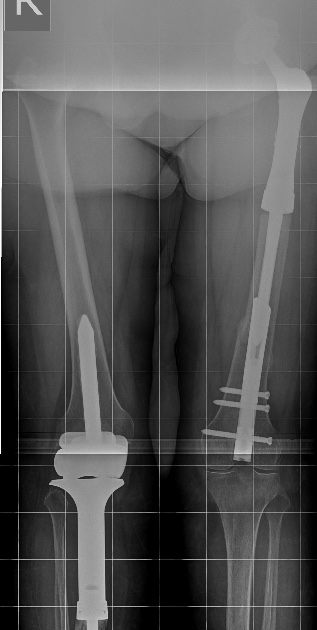

[Ortho] Перипротезный перелом

Имя     : 1.jpg

Тип     : image/jpeg

Размер  : 61793 байтов

Url     : http://weborto.net:8080/pipermail/ortho/attachments/20150205/ae2825c5/attachment-0002.jpg